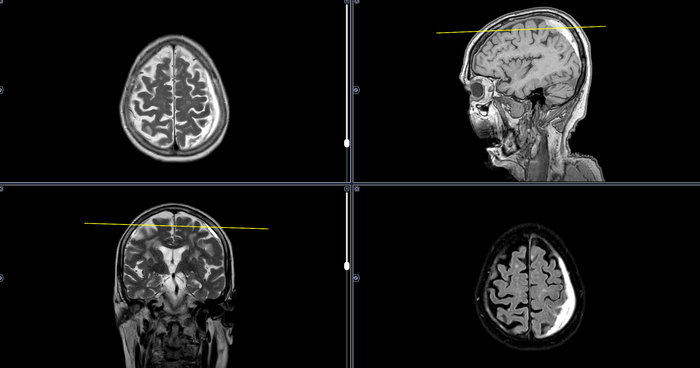

МРТ-Хроническая субдуральная гематома

Субдуральная гематома – это скопление крови между твердой мозговой оболочкой и паутинной оболочкой головного мозга.

МРТ стадии субдуральной гематомы:

Острая стадия (до 3 суток)

МРТ в режиме T1: изоинтенсивный или слегка гипоинтенсивный сигнал.

МРТ в режиме T2: выраженный гипоинтенсивный сигнал из-за дезоксигемоглобина.

FLAIR: гиперинтенсивный сигнал (из-за окружающего отека).

DWI (диффузионно-взвешенные изображения): может быть гиперинтенсивным из-за высокой вязкости крови.

2. Ранняя подострая стадия (3–7 дней)

T1: становится гиперинтенсивным из-за образования метгемоглобина.

T2: остается гипоинтенсивным (метгемоглобин еще внутри клеток).

FLAIR: гиперинтенсивный сигнал гематомы и окружающего отека.

3. Поздняя подострая стадия (1–3 недели)

T1: сохраняет гиперинтенсивность (метгемоглобин становится внеклеточным).

T2: становится гиперинтенсивным (из-за лизиса эритроцитов и выхода метгемоглобина).

FLAIR: гиперинтенсивность сохраняется.

4. Хроническая стадия (после 3 недель)

T1: сигнал снижается, может быть изо- или гипоинтенсивным.

T2: гипоинтенсивный сигнал по краям (из-за отложения гемосидерина) и гиперинтенсивный в центре (при наличии жидкости).

FLAIR: гиперинтенсивность уменьшается, но может сохраняться по периферии.

GRE/SWI: четкая гипоинтенсивная кайма (гемосидерин).

Анамнез: возрастная пациентка, жалобы на частые головные боли, особенно в области затылка. Падала в ванной на плитку, ударилась задней частью головы 7 мес. назад.

МР-картина хронических субдуральных гематом обоих полушарий головного мозга(более крупная слева). МР- признаки очаговых изменений головного мозга, сосудистого генеза ( микроангиопатия, Fazekas 3). Диффузная церебральная атрофия 1 ст. ( по шкале GCA).